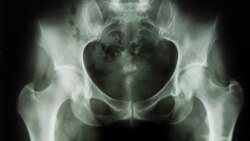

អាហារ​និង​ការ​ហាត់​ប្រាណ​ជួយ​ទប់ស្កាត់​ជំងឺ​ពុក​ឆ្អឹង

វ៉ាស៊ីនតោន៖ វិធី​សាមញ្ញ​ពីរ​ដែល​អាច​ទប់​ស្កាត់​ជំងឺ​ពុក​ឆ្អឹង​គឺ​ទី​១ ការ​ទទួល​ទាន​ម្ហូប​អាហារ​ដែល​មាន​ជាតិ​កាល់ស្យូម​និង​វីតាមីនដេ ដែល​ម្ហូប​ទាំង​នោះ​រួមមាន​ ផលិតផល​ទឹក​ដោះ​គោ បន្លែ​ដែល​មាន​ស្លឹក​ពណ៌បៃ​តង​ ត្រី យ៉ាអួ​ (yoghurt) និង​តៅហ៊ូ​ ជាដើម ហើយ​ទី​២​ ការ​ហាត់​ប្រាណ ដូច​ជា​ការ​ដើរ​លឿន រត់​តឹកៗ រាំ ថៃជី ឬ យោហ្គា និង​ជិះកង់។ល។ នេះ​បើ​តាម​សម្តី​របស់​លោក​វេជ្ជបណ្ឌិត តាំង តេកហុង ខែ្មរ​អាមេរិកាំង​ដែល​កំពុង​ធ្វើ​ការ​និង​រស់​នៅ​ទីក្រុង Jackson Ville រដ្ឋ​ហ្វ្លរីដា​ សហរដ្ឋ​អាមេរិក ដែល​បានមាន​ប្រសាសន៍​ក្នុងកម្មវិធី​ហេឡូវីអូអេ​កាល​ពី​ថ្ងៃ​ទី ២០ ខែ​ កុម្ភៈនេះ។

«ស្ត្រី​នៅ​មាន​រដូវ​និងបុរស​ដែល​មាន​អាយុ​ក្រោម​៧០ឆ្នាំ ​ក្នុង​មួយ​ថ្ងៃ​ត្រូវ​ការ​ជាតិ​កាល់ស្យូម​ចំនួន​១.០០០mg និង​វីតាមីន​ដេ ៦០០mg IU។ ស្ត្រី​អស់​រដូវ​និងបុរស​ដែល​មាន​អាយុ​លើស​៧០ឆ្នាំ​ក្នុង​មួយ​ថ្ងៃ​ត្រូវ​ការជាតិ​កាល់ស្យូម​ចំនួន​១.២០០mg និង​វីតាមីន​ដេ ៨០០mg IU»។

លោក​វេជ្ជ​បណ្ឌិត តាំង តេកហុង​ មាន​ប្រសាសន៍​ថា គោល​បំណង​នៃ​ការ​ព្យាបាល​ជំងឺ​ពុក​ឆ្អឹង​គឺ​គ្រប់​គ្រង​ការ​ឈឺចាប់​ដោយ​សារ​ជំងឺ​ពុក​ឆ្អឹង ការ​ពន្យឺត​ ឬ​បញ្ឈប់​ការ​សឹក​នៃ​ឆ្អឹង ការ​ទប់ស្កាត់​ការ​ប្រេះ​ស្រាំ​ឆ្អឹងដោយ​ការ​ប្រើ​ឱសថដើម្បី​ពង្រឹង​ឆ្អឹង និងការជៀសវាង​ការ​ដួល​ដែល​អាច​បណ្តាល​ឲ្យ​ប្រេះ​ស្រាំ​ឆ្អឹង។

លោក​វេជ្ជបណ្ឌិត តាំង តេកហុង​ បាន​ផ្តល់​យោបល់ថា ឱសថ​ Bisphosphonates​ ត្រូវ​បាន​ប្រើ​ជា​ឱសថ​ចម្បង​សម្រាប់​ការ​ពារ​និង​ទប់​ស្កាត់​ជំងឺ​ពុក​ឆ្អឹង​សម្រាប់​ស្ត្រី​អស់​រដូវ។ ឱសថ​ផ្សេង​ទៀត​រូម​មាន​Alendronate (Fosamax), Ibandronate (Boniva), Risendronate (Actonel), ហើយ​ឱសថ ​Calcitonin ដែល​បន្ថយការ​សឹក​ឆ្អឹង និង​បន្ថយ​ការ​ឈឺចាប់​ក្នុង​ឆ្អឹង ឱសថ Estrogen ដែល​ពេល​នេះគេ​មិន​សូវ​ប្រើសម្រាប់ការ​ពារ​ជំងឺ​ពុក​ឆ្អឹង​ទេ ឱសថ Reloxifene, Parathyroid, Teriparatide or Forteo ដែល​ជួយ​រៀបចំ​កសាង​ឆ្អឹង និង​ឱសថ Denosumate។

លោកវេជ្ជបណ្ឌិត​ តាំង តេកហុង​ មាន​ប្រសាសន៍​ថា ឆ្អឹង​មនុស្ស​លូត​លាស់រហូត​ដល់​អាយុ​៣០​ឆ្នាំ។ ដូច្នេះ​លោកផ្តល់​យោបល់​ថា មនុស្ស​ត្រូវ​ការ​របប​អាហារ​ដែល​មាន​វីតាមីន​គ្រប់​គ្រាន់​ជា​ពិសេស​វីតាមីនដេ​និង​ជា​តិ​កាល់ស្យូម​ និងហាត់​ប្រាណទៀត​ទាត់៕